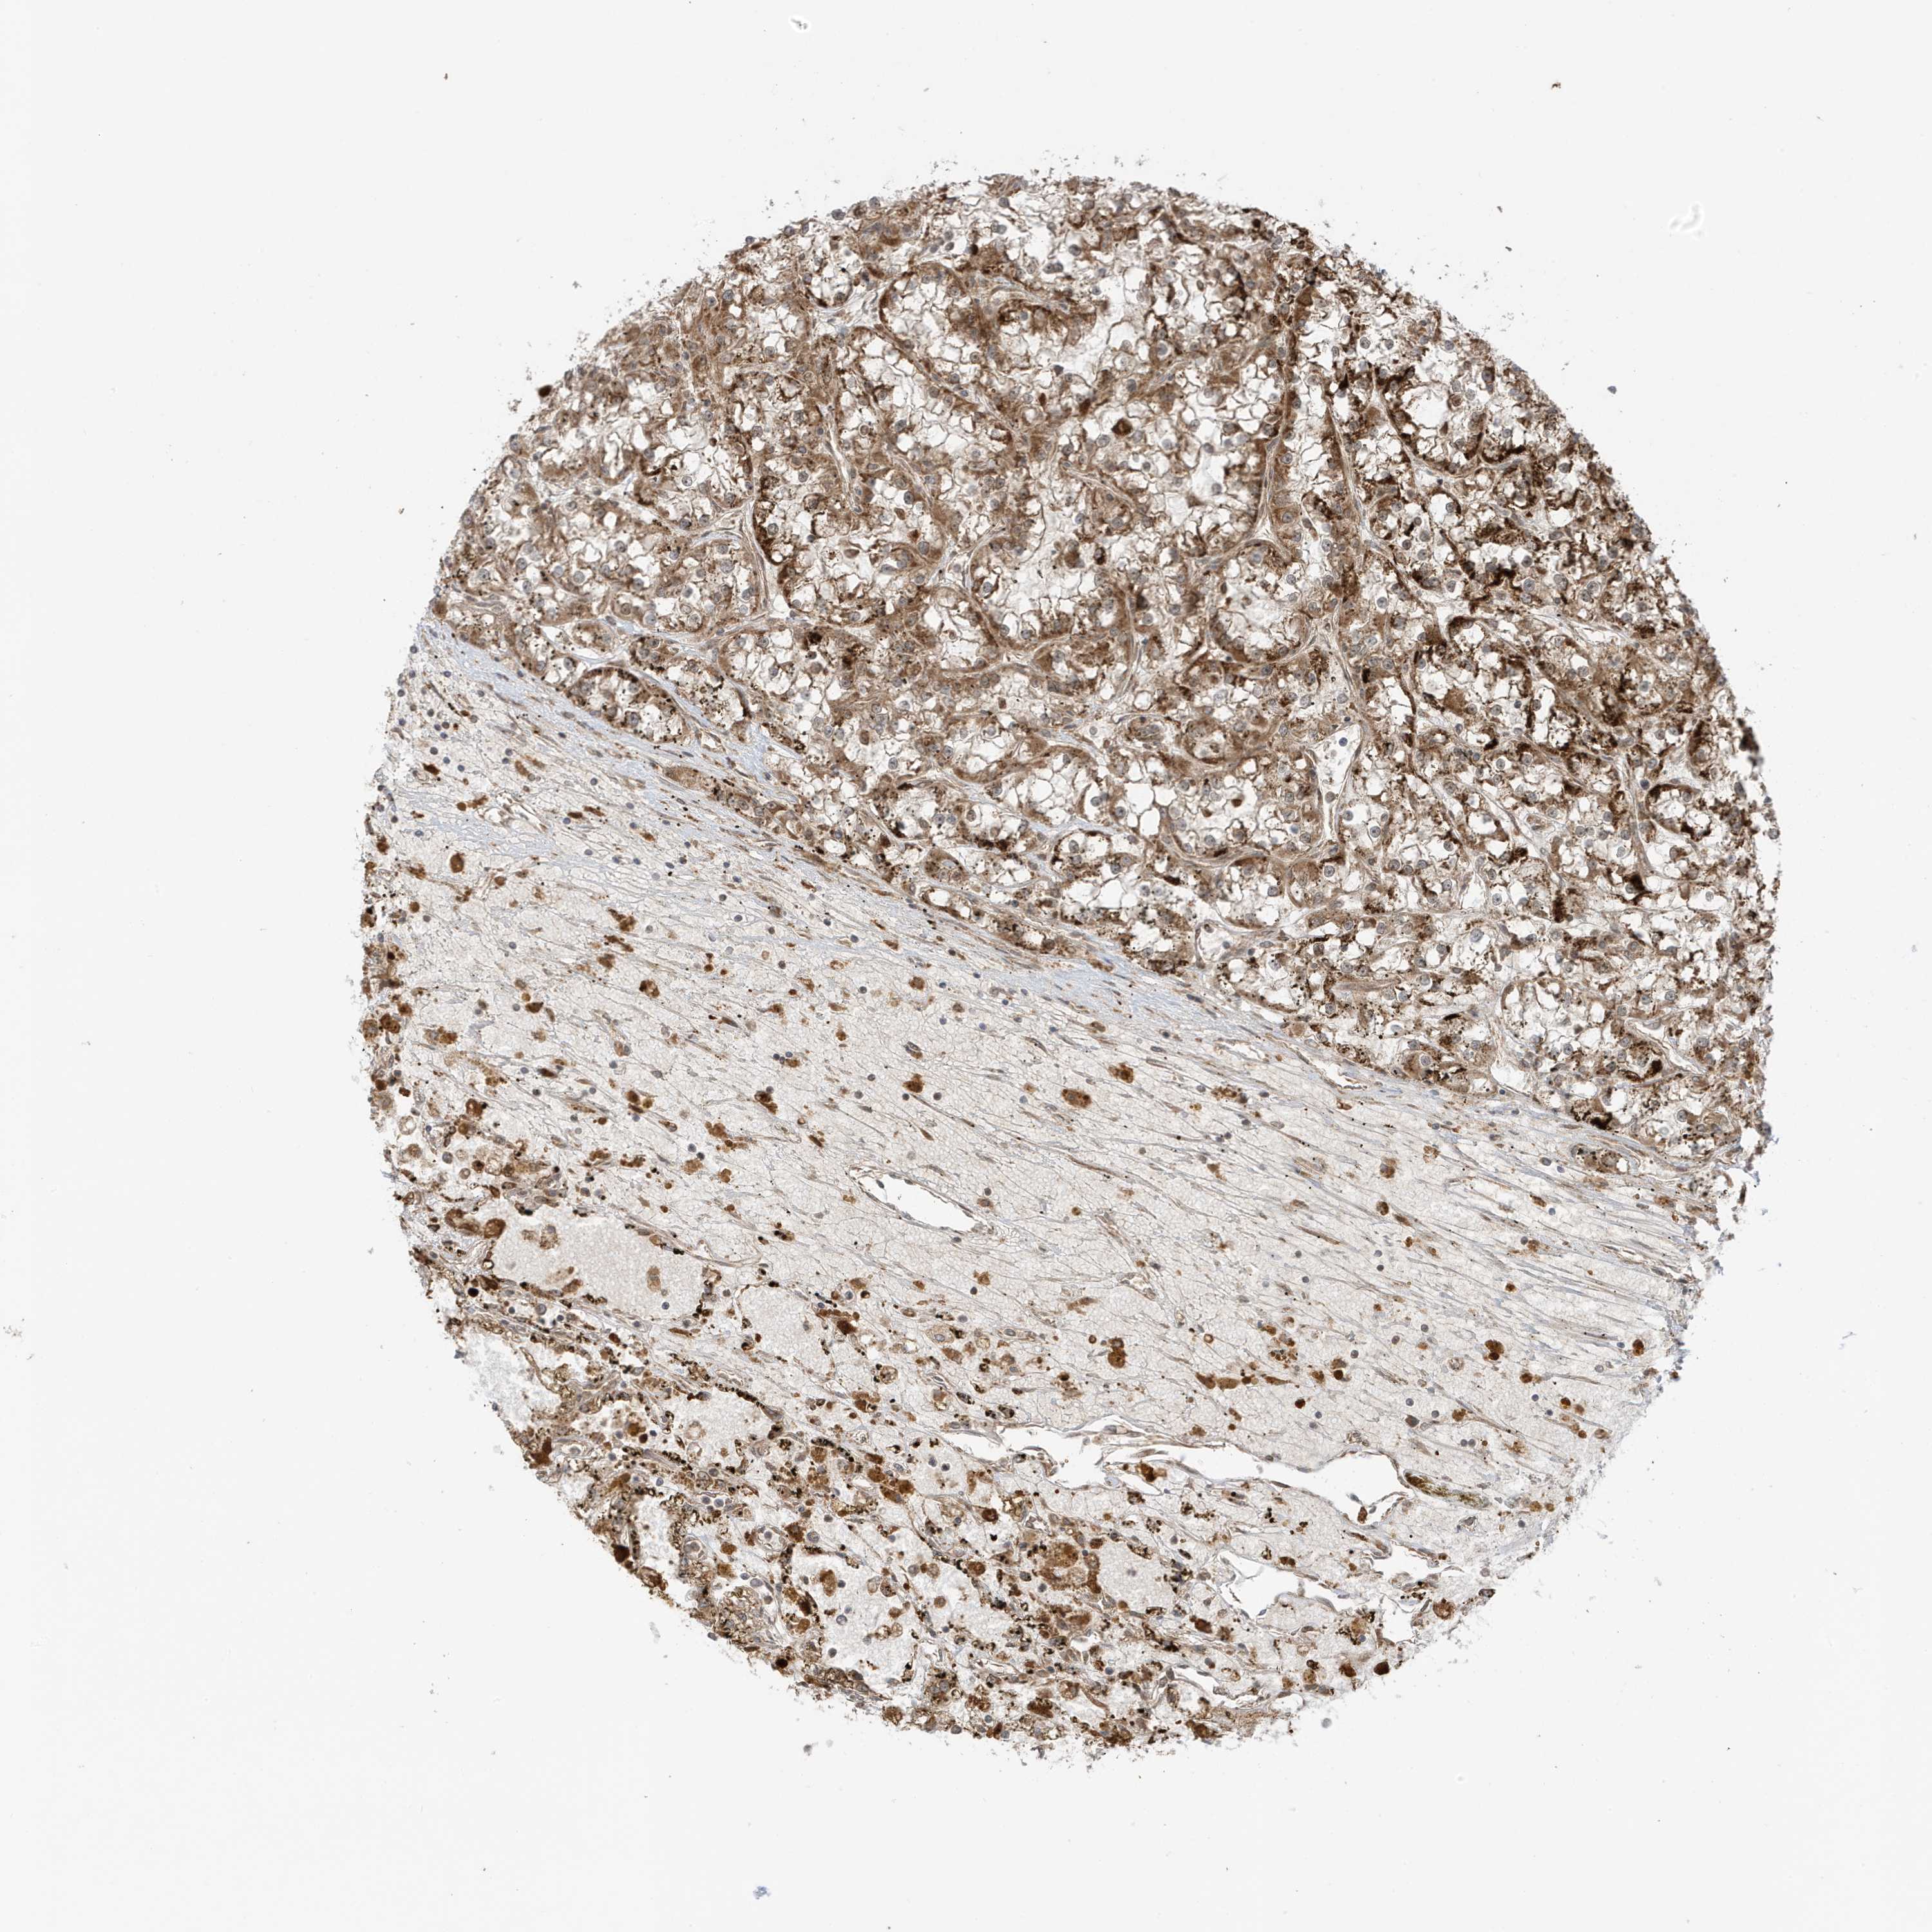

KIDNEY RENAL CLEAR CELL CARCINOMA (TCGA) - Interactive survival scatter ploti

The Survival Scatter plot shows the clinical status (i.e. dead or alive) for all individuals in the patient cohort, based on the same data that underlies the corresponding Kaplan-Meier plots. Patients that are alive at last time for follow-up are shown in blue and patients who have died during the study are shown in red.

The x-axis shows the expression levels (FPKM) of the investigated gene in the tumor tissue at the time of diagnosis. The y-axis shows the follow-up time after diagnosis (years). Both axes are complimented with kernel density curves demonstrating the data density over the axes. The top density plot shows the expression levels (FPKM) distribution among dead (red) and alive patients (blue). The right density plot shows the data density of the survived years of dead patients with high and low expression levels respectively, stratified using the cutoff indicated by the vertical dashed line through the Survival Scatter plot. This cutoff is automatically defined based on the FPKM cutoff that minimizes the p-score. The cutoff can be changed by dragging the vertical line or by entering a cutoff value in the square labeled "Current cut-off".

Under the Survival Scatter plot the p-score landscape (black curve; left axis) is shown together with dead median separation (red curve; right axis). Dead median separation is the difference in median mRNA expression between patients who have died with high and low expression, respectively. It is calculated as follows: median FPKM expression of dead patients with high expression - median FPKM expression of dead patients with low expression. This is intended to aid the user in visually exploring custom cutoffs and the associated p-scores and dead median separation.

Individual patient data is displayed and can be filtered by clicking on one or more of the category buttons on the top of the page. Categories describing expression level and patient information include: high, low, alive, dead, female, male and tumor stages. The scale of the x-axis can be toggled between linear and log-scale by clicking on the "x log" button. Mouse-over function shows TCGA ID, patient information and mRNA expression (FPKM) for each patient.

& Survival analysisi

Kaplan-Meier plots summarize results from analysis of correlation between mRNA expression level and patient survival. Patients were divided based on level of expression into one of the two groups "low" (under cut off) or "high" (over cut off). X-axis shows time for survival (years) and y-axis shows the probability of survival, where 1.0 corresponds to 100 percent.

DHX36 is potential prognostic, high expression is favorable in Kidney Renal Clear Cell Carcinoma (TCGA)

Best expression cut offi

Based on the FPKM value of each gene, patients were classified into two groups and association between prognosis (survival) and gene expression (FPKM) was examined. The best expression cut-off refers the FPKM value that yields maximal difference with regard to survival between the two groups at the lowest log-rank P-value. Best expression cut-off was selected based on survival analysis .

When clicking on this number, the vertical dashed line indicating cut-off, the interactive survival plot, and the Kaplan-Meier curve will be adjusted to show results based on the best expression cut-off.

: 6.13

P scorei

Log-rank P value for Kaplan-Meier plot showing results from analysis of correlation between mRNA expression level and patient survival.

N/A

TCGA RNA samplesi

RNA-seq data is reported as average FPKM (number Fragments Per Kilobase of exon per Million reads), generated by the The Cancer Genome Atlas (TCGA) .

Normal distribution across the dataset is visualized with box plots, shown as median and 25th and 75th percentiles. Points are displayed as outliers if they are above or below 1.5 times the interquartile range. FPKM values of the individual samples are presented next to the box plot.

Average pTPM 11.7

Number of samples 521